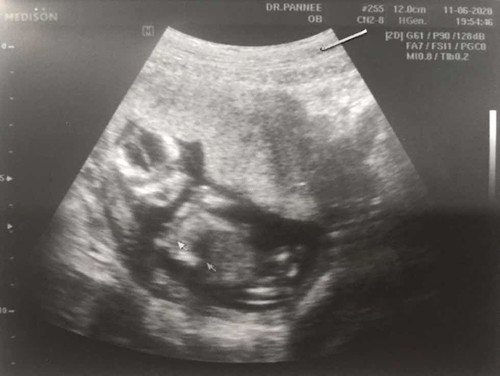

12w4d ครั้งแรกกลับการเห็นลูกเป็นรูปเป็นร่างตื่นเต้นที่สุด ดีใจที่สุด คุณหมอบอกน้องตัวยาวใหญ่ ให้คุณแม่กินปกติไม่ต้องเยอะ หลีกเลี่ยงของหวาน

โตจังเลย เกือบเต็มมดลูกคุณแม่เลยลูก ☺️💕